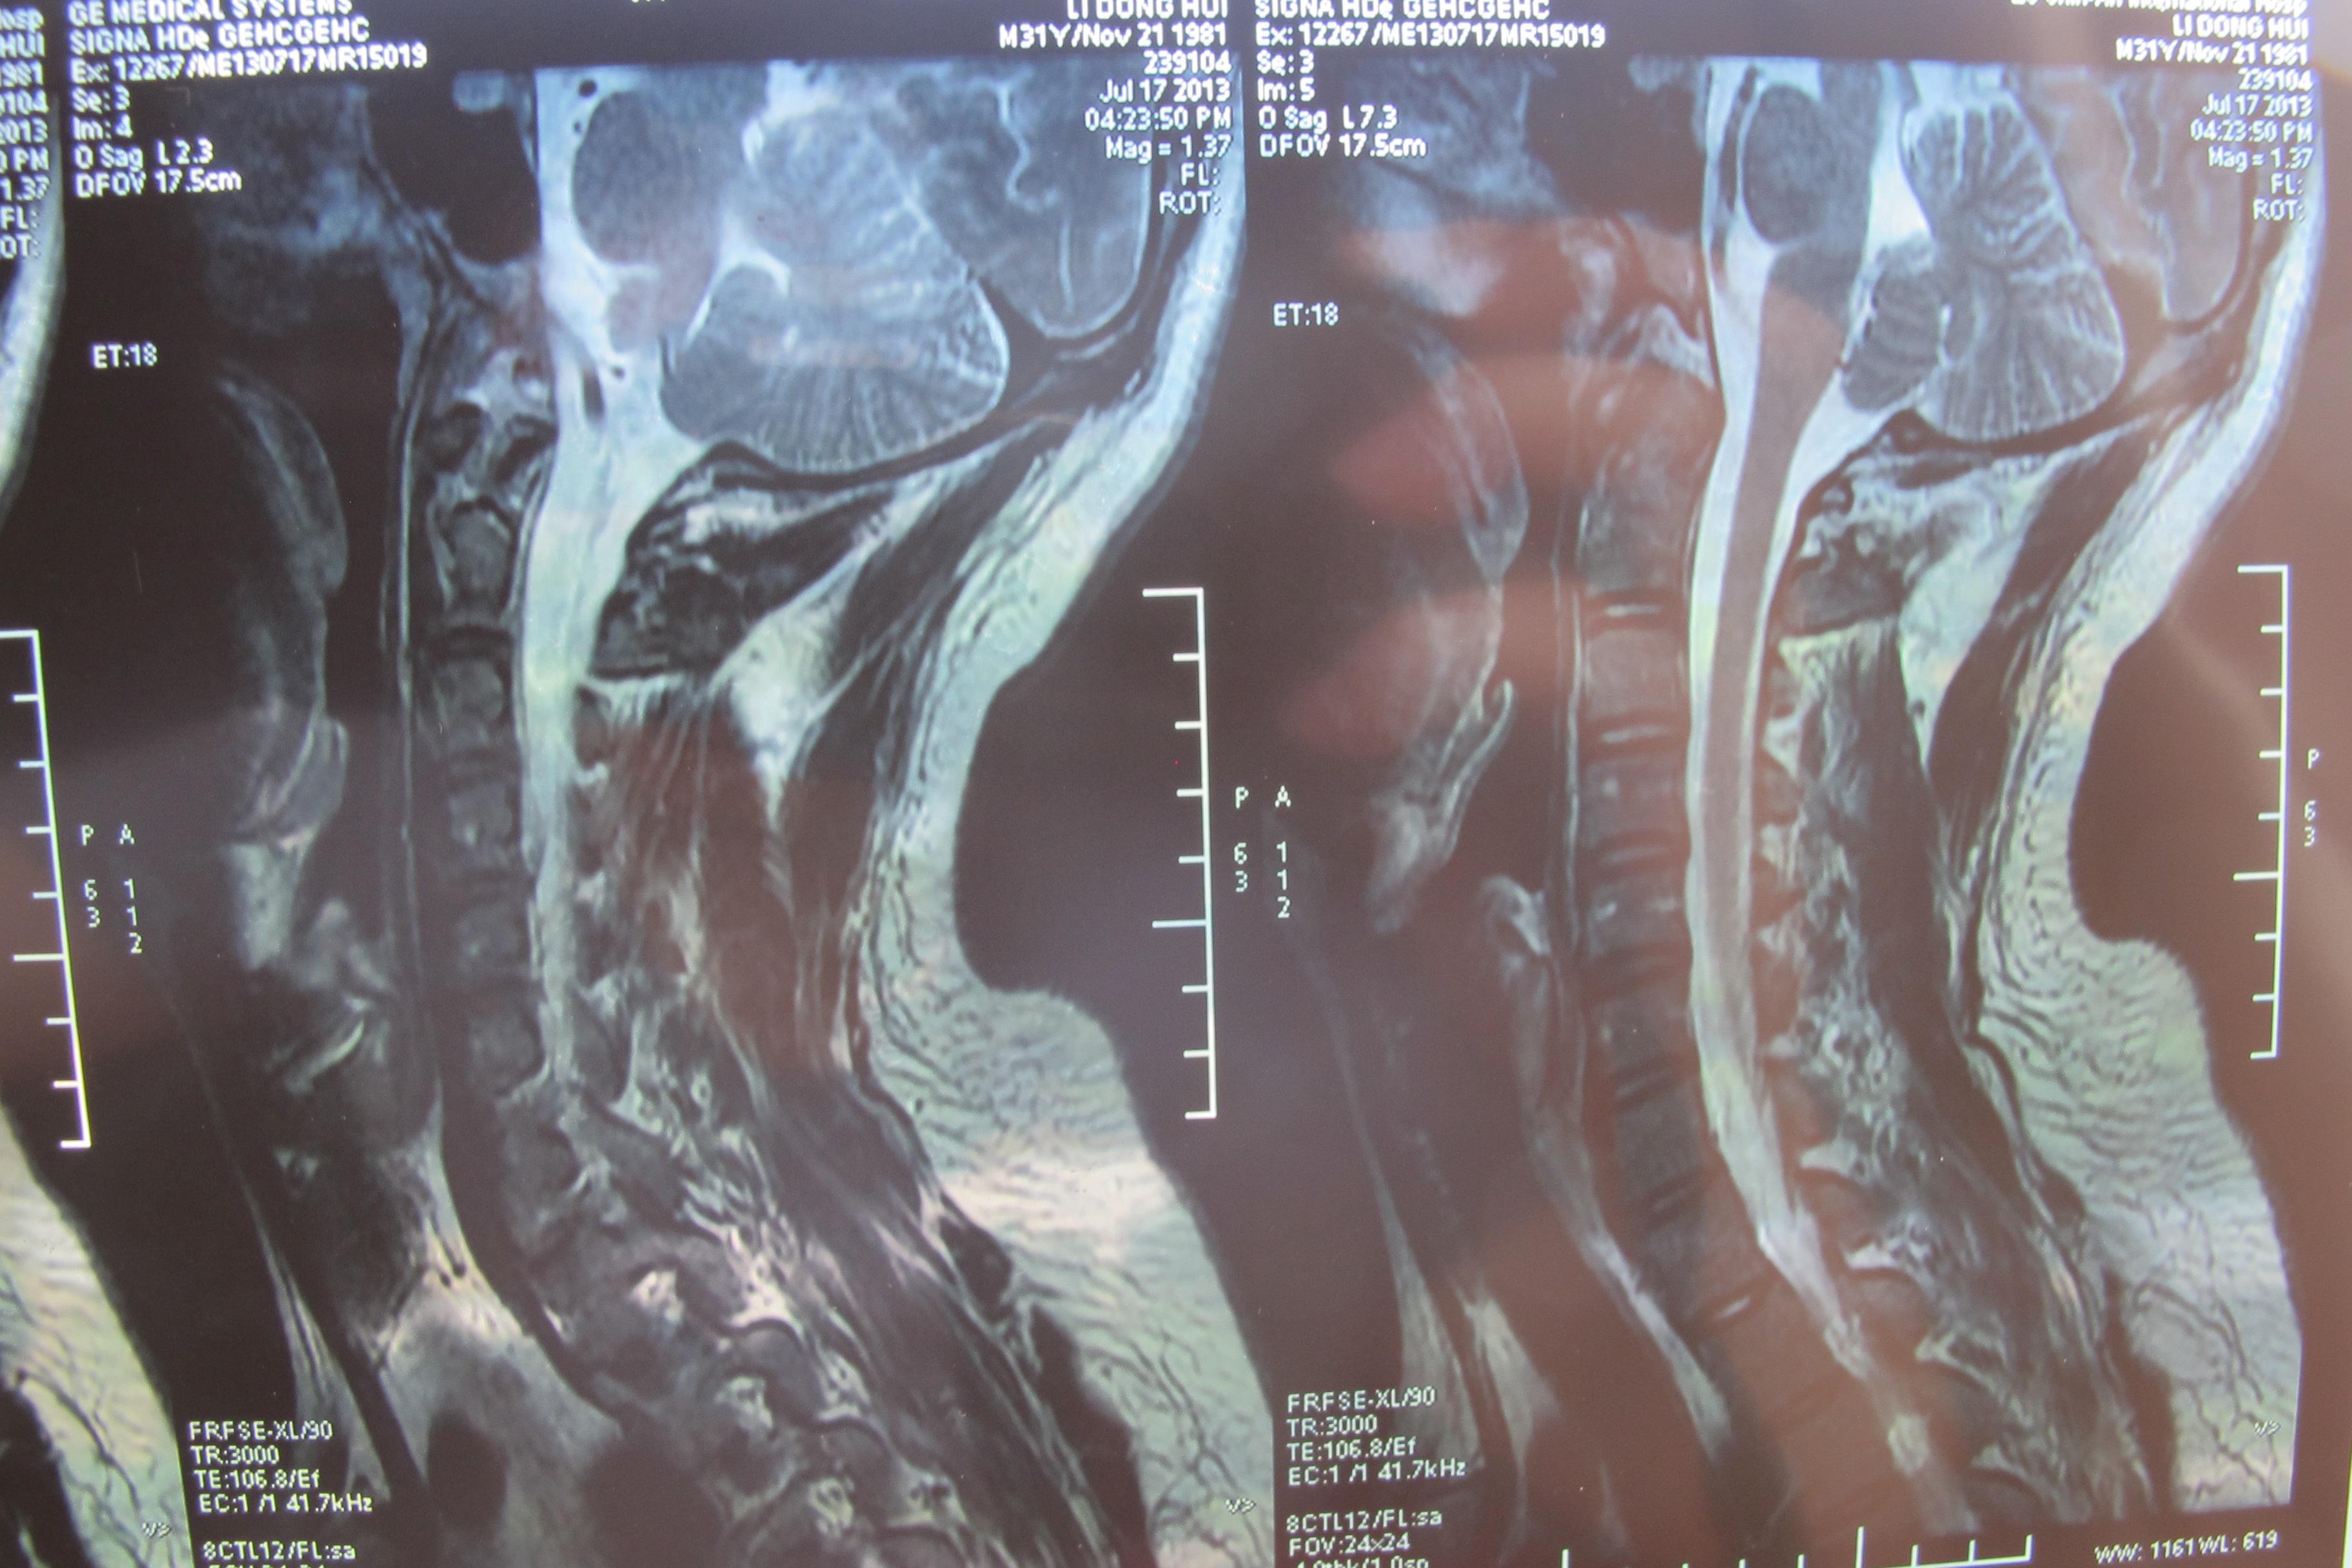

年轻多节段椎间盘突出颈椎病的治疗【1119】 [精华]

图片尺寸3648x2736

颈椎核磁片显示:颈4,5,6,7位颈椎间盘突出!